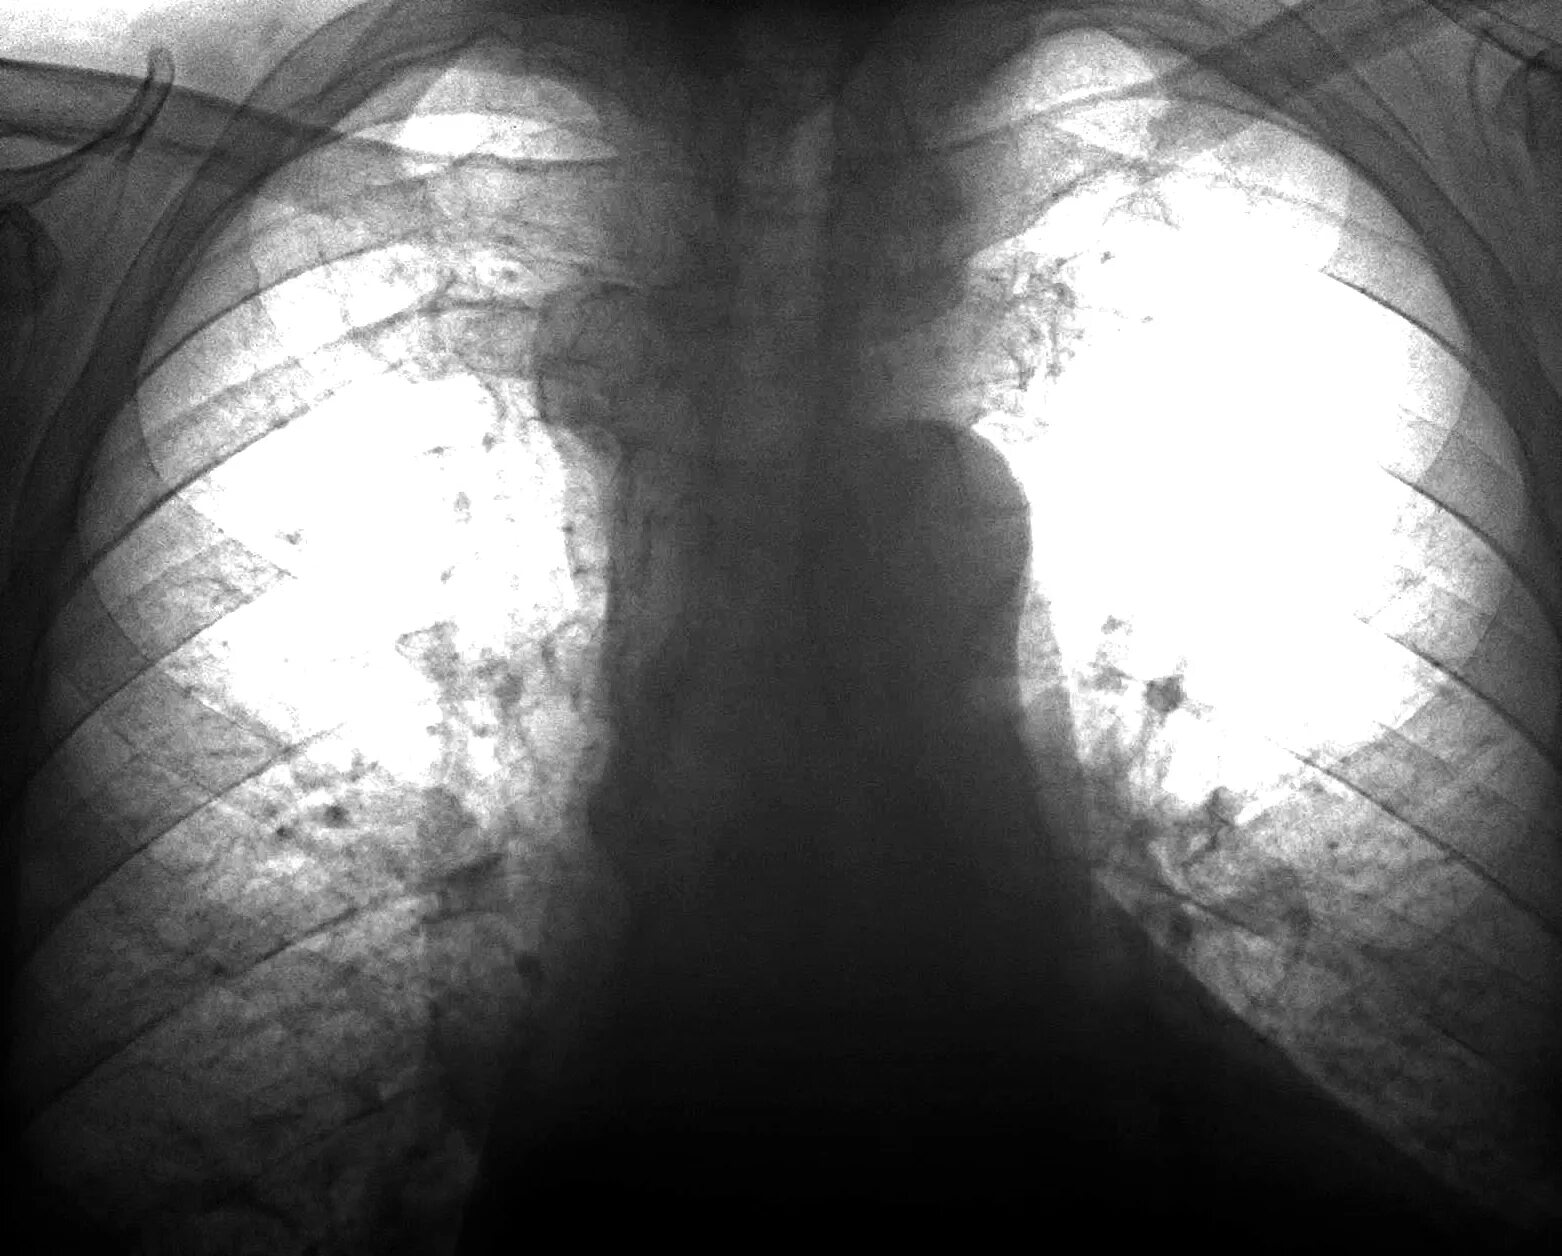

Обызвествление в проекции